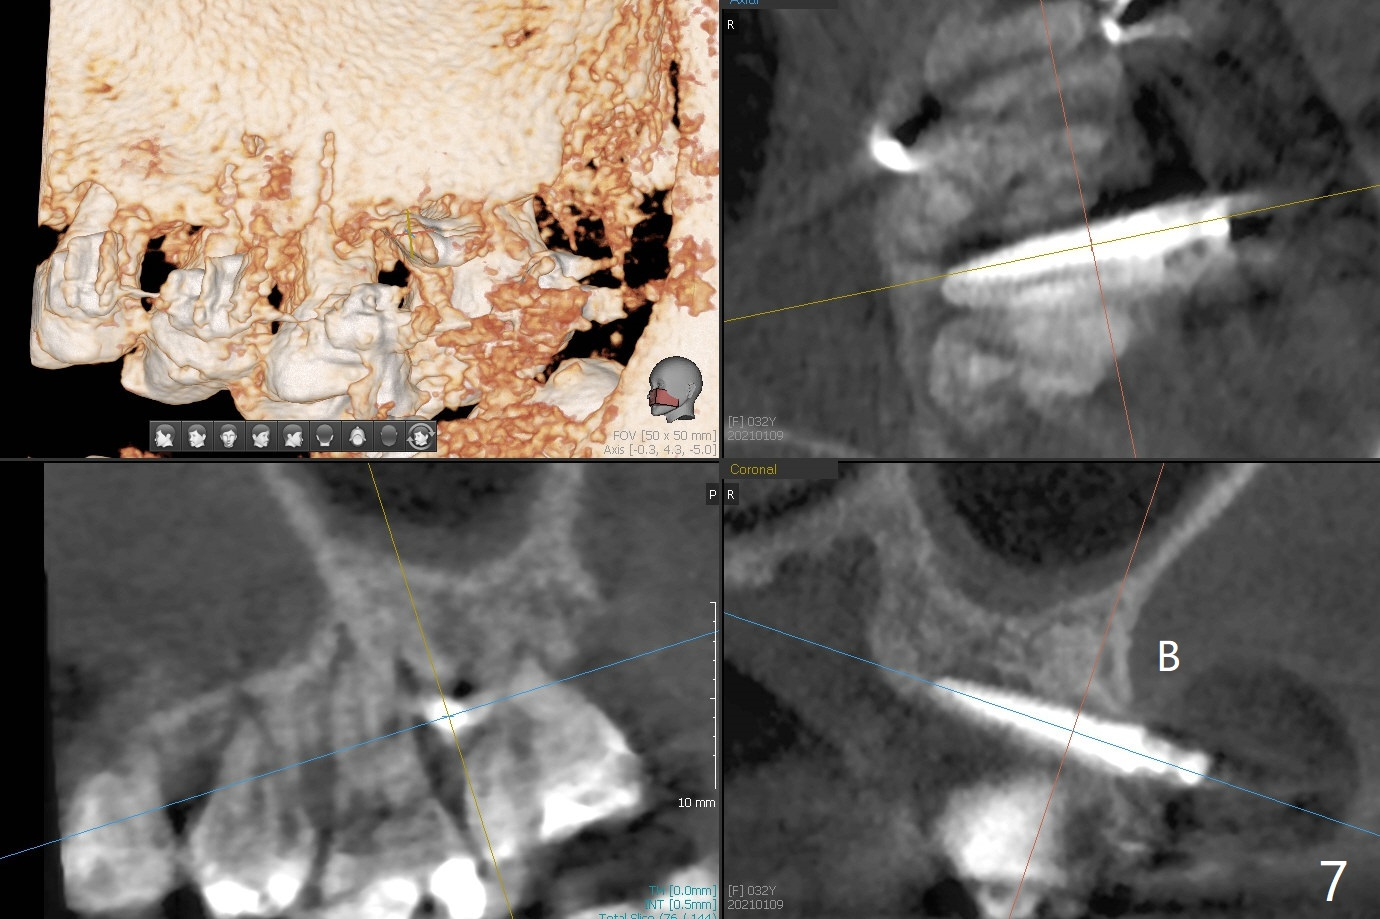

矫正器放置后一个月,正好有充裕时间,匆忙研究全景片(最好CT),好像左上6近中间隙大,近中颊侧,远中腭侧似乎是种植位点(图一:白圆圈),植入越高越宽,不容易伤及邻牙牙根。但是微型植体种植原则是必须种植在角化龈,减少炎症(以前不明白为什么)。当植体在移动牙龈植入时(图二:白箭头),牙龈浮起来,估计非角化牙龈也不能与植体产生紧密结合。取出后,完全可以在6近中颊侧角化龈植入,但是仔细检查发现远中颊侧角化龈更宽,所以在那里扎根(图二:黑箭头),因此腭侧就得选择近中(图三)。微型植体可以即刻使用,power chains常滑脱,压迫牙龈,在这个病例很可能进入远中牙间隙,所以需要在远中边缘嵴加树脂(图四,五:* (1.6x8mm))。第二天远中颊侧植体松动,取出后,插入2x10毫米一段式植体,仍然松动(图六)。CT显示植体下缘穿破牙槽骨(图七,骨质吸收严重与图八近中牙槽骨高度对比)。如果在近中颊侧重新植入微型植体,必须使用6毫米长植体(图九),所以最好在远中颊侧重新植入(图十:红色),缺损区(黑色)植骨。在使用14 niti时,左下7松动,病人同意拔除8,以后后推7,然后6种植(图十一:(左上8已拔除(x))),同时左上6远中植骨,左下8远中牙槽窝放置浸泡PRF液体胶原塞(图十二:1),近中牙槽窝粘性骨粉(2),最后牙槽窝上部PRF膜(3),PGA缝线。可能需要Cytoplast。